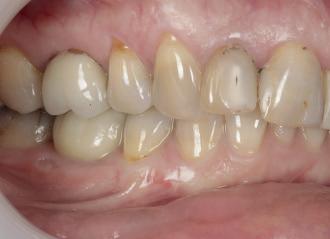

Marketing and branding yourself using social media platforms is essential as a selfemployed individual. Breaking that fear and anxiety of showcasing and promoting your before-and-after work, and highlighting patient testimonials on social media is not only important to demonstrate your skillset as a young dentist but also to boost your reputation and recognition for welcoming new patients. Having been fortunately selected as a finalist for multiple awards in the past including this year’s Dental Awards, it has not only boosted my esteem and confidence as a young dentist, but has encouraged me to keep steering this journey forward for the benefit of my patients’ healthcare and my own ability to provide excellent dentistry. Plus, receiving a shiny plaque to put on the wall for patients to see provides a confidence boost for them, as well as myself.

I personally use Instagram for my content. I was always hesitant to post images of my work in fear of being judged by other dentists, but eventually overcame this and told myself to have confidence in the quality of my work and just do it. That mindset has worked in my favour since. Sharing before-and-after cases (with patient consent), posting educational videos about common procedures, and fun moments behind the scenes to make your practice feel welcoming speaks for itself. Be sure to engage with your audience by answering questions, responding to comments and showing that you care.